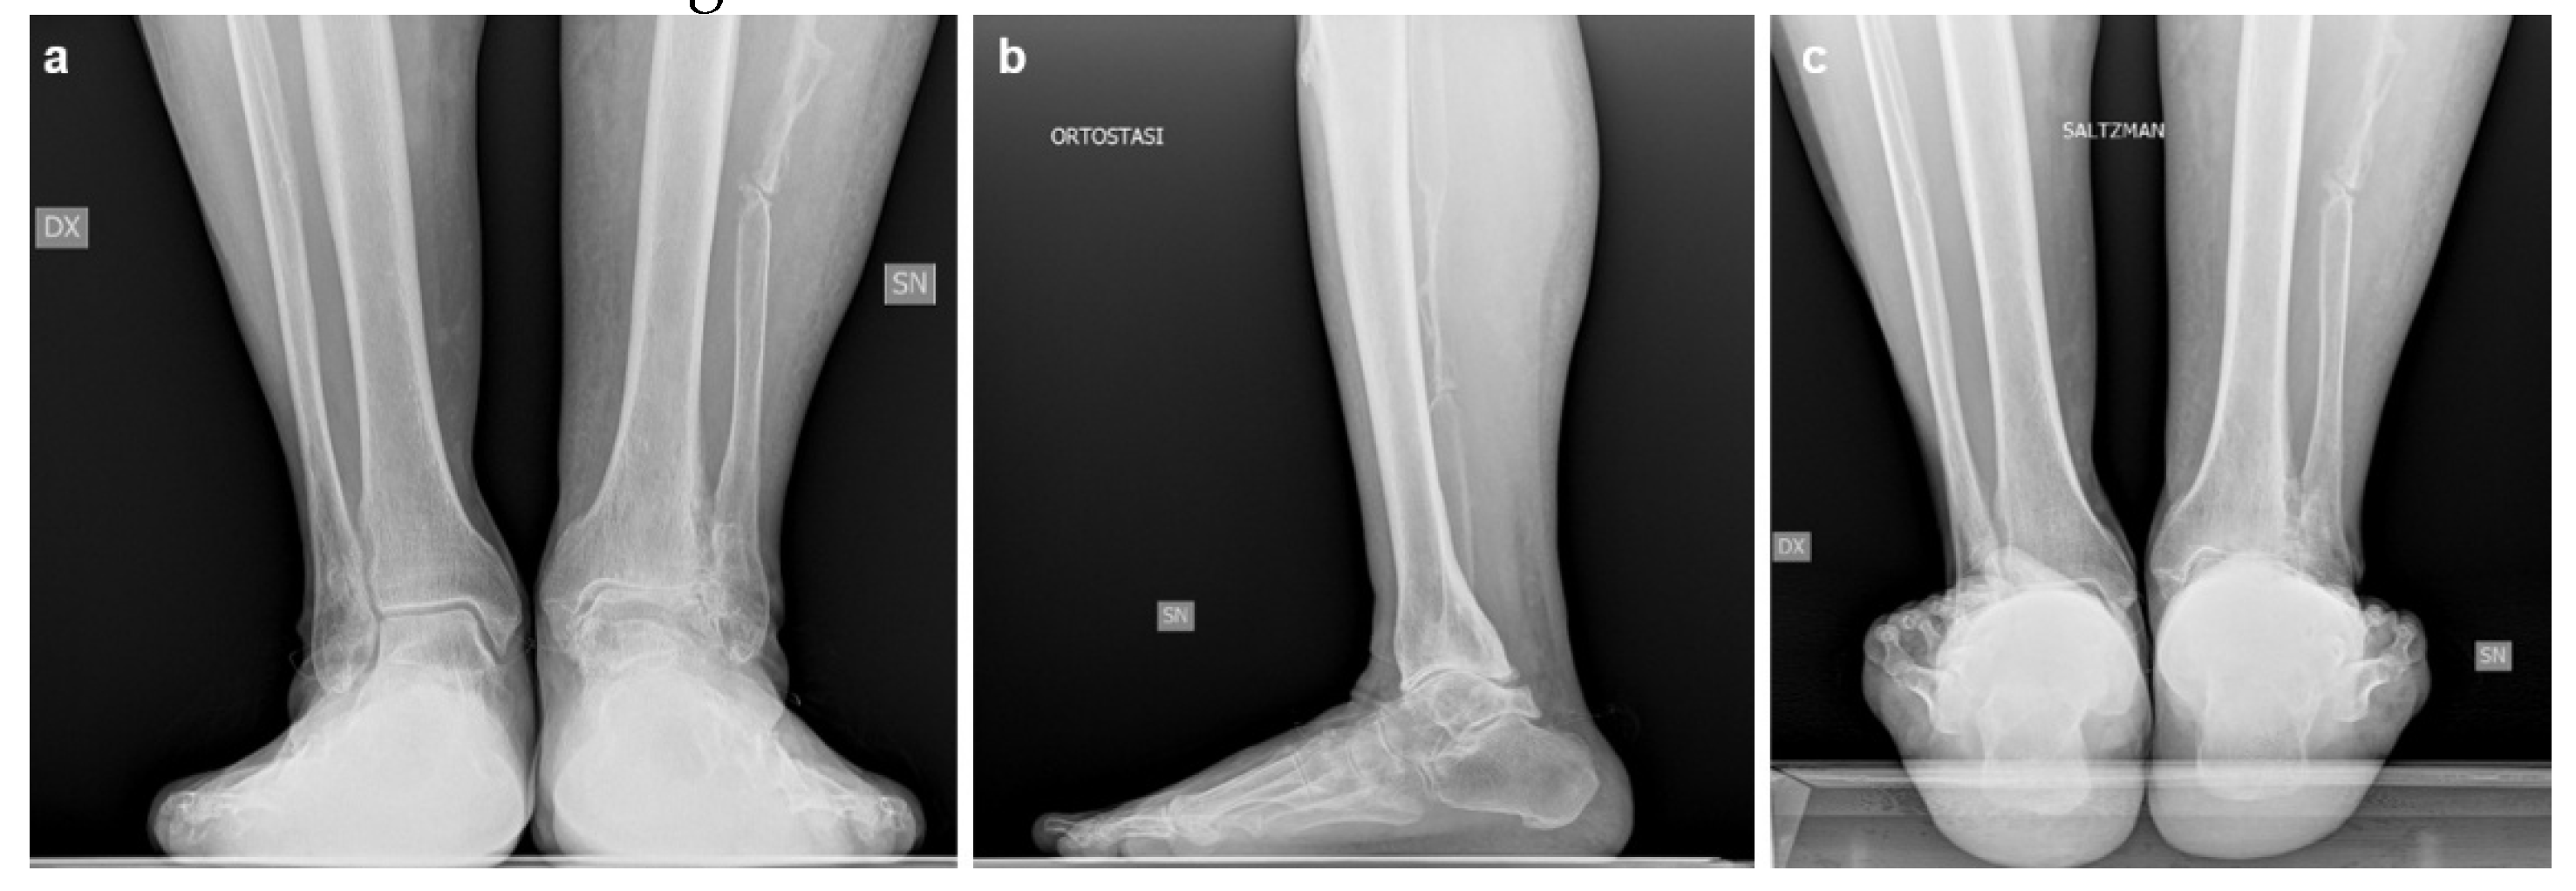

Imaging, including bilateral weight-bearing X-rays (Figure 4) and WBCT (Figure 5), demonstrated end-stage tibiotalar osteoarthritis (Kellgren–Lawrence grade 4[8]) with distal tibial and distal fibular bone deformity. The ankle showed a valgus alignment with posterior shift of the talus. Early degenerative changes were also observed in the talonavicular and subtalar joints. The midshaft of the fibula displayed residual deformity from previous surgical procedures. Radiographic measurements are summarized in Table 2. The patient gave informed consent for the publication of his clinical details and images.

Figure 4. Preoperative weight-bearing radiographs of Case two: a) anteroposterior view; b) lateral view; c) Saltzman view.